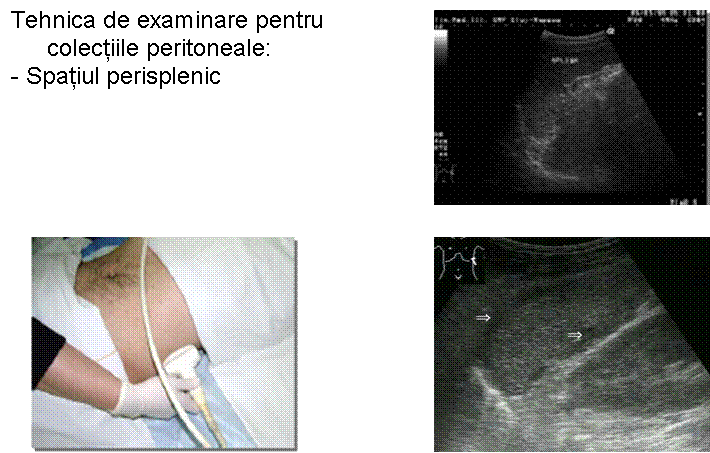

TRAUMATISM ABDOMINAL EXAMINARE FAST